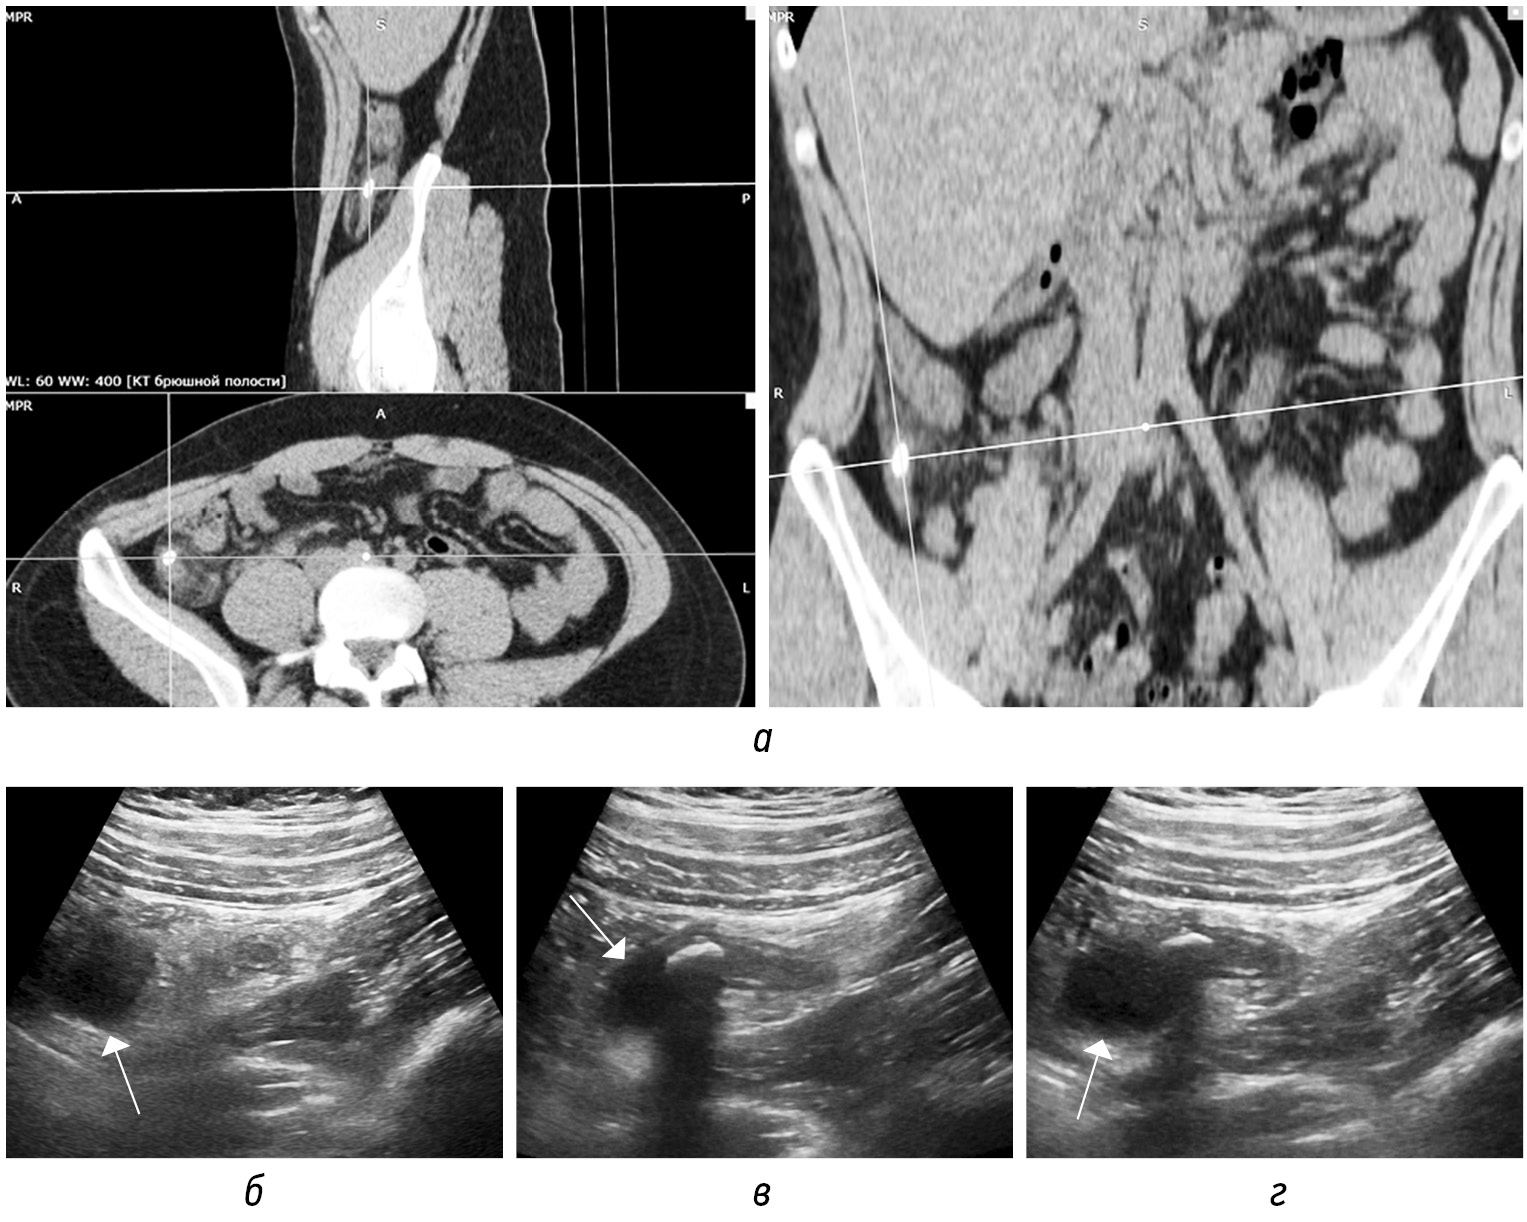

В наши дни наиболее часто используемым протоколом является нативная КТ живота и таза с последующим внутривенным введением контрастного вещества и (иногда) пероральным контрастированием. Рекомендуется использовать однофазное, а не многофазное сканирование, чтобы избежать любой дополнительной дозы [21]. Наиболее информативной для оценки является портовенозная фаза [3] (рис. 1, а–е).

Рис. 1. На КТ-изображениях в аксиальной плоскости в нативную (а, г), артериальную (б, д), портовенозную (в, е) фазы на двух уровнях демонстрируется накопление контрастного вещества стенками аппендикулярного отростка (стрелка) в разные постконтрастные фазы в сравнении с нативной. В просвете аппендикса на фоне жидкостного содержимого визуализируется феколит (пунктирная стрелка)

Fig. 1. CT images in the axial plane in the native phase (а, г), arterial phase (б, д), portovenous phase (в, е) at two levels demonstrate the accumulation of contrast agent by the walls of the appendicular process (arrow) in different post-contrast phases in comparison with the native. In the lumen of the appendix, fecal matter is visualized against the background of liquid contents (dotted arrow)